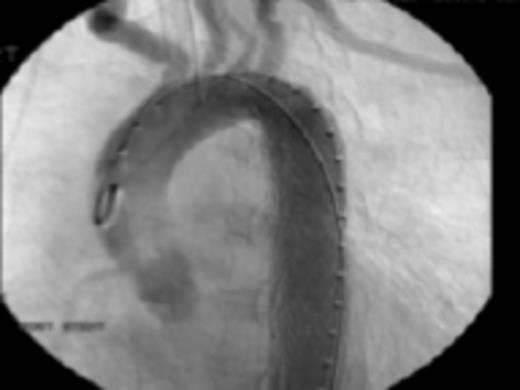

Fig 4: Post endovascular stenting angiography showing appropriate seal without leaks or extravasation of contrast

Her past medical history of considerable GI bleeds and her significant fall risk made her a poor candidate for continued anti-coagulation therapy. The appropriateness of the lesion involved and her risk for further embolic events guided selection of endovascular technique for treatment. Exclusion was performed by a 26mm × 10cm thoracic aortic stent graft with balloon angioplasty. Post-procedure angiography confirmed position of the graft distal to the origins of the great vessels and did not demonstrate any leaks. Subsequently, she progressed well and was discharged in stable condition on warfarin and clopidogrel.